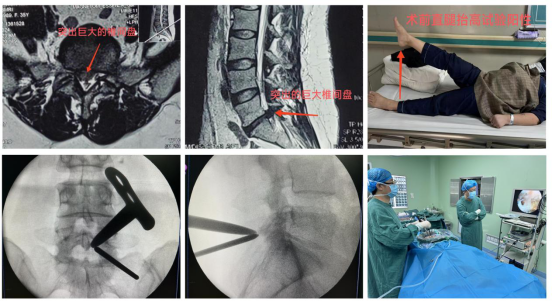

周至县人民医院骨科近期收治了一位35岁女性患者,主诉“右下肢抽痛、麻木半年,加重2月”,行走约50米后,右下肢疼痛难忍,严重影响生活质量。靳占奎副主任医师对患者进行了一系列检查和严格的鉴别诊断,认定该患者“腰椎间盘突出症”诊断明确,且患者经过半年以上的保守治疗无显著疗效,具有明确手术指征。靳占奎副主任医师指导县医院充分完善UBE技术必备的硬件条件,为患者顺利实施了“微创单侧双通道脊柱内镜下腰椎间盘髓核摘除术”。术后患者右下肢疼痛缓解,患者非常满意。

微创单侧双通道脊柱内镜(UBE)技术是治疗腰椎间盘突出症的经典微创手术方式,相较于其它微创手术,该技术入路更接近开放手术,学习曲线相对平缓,镜下视野更全面,操作通道可以应用类似开放手术的器械,安全性高。该手术目前是欧美视频